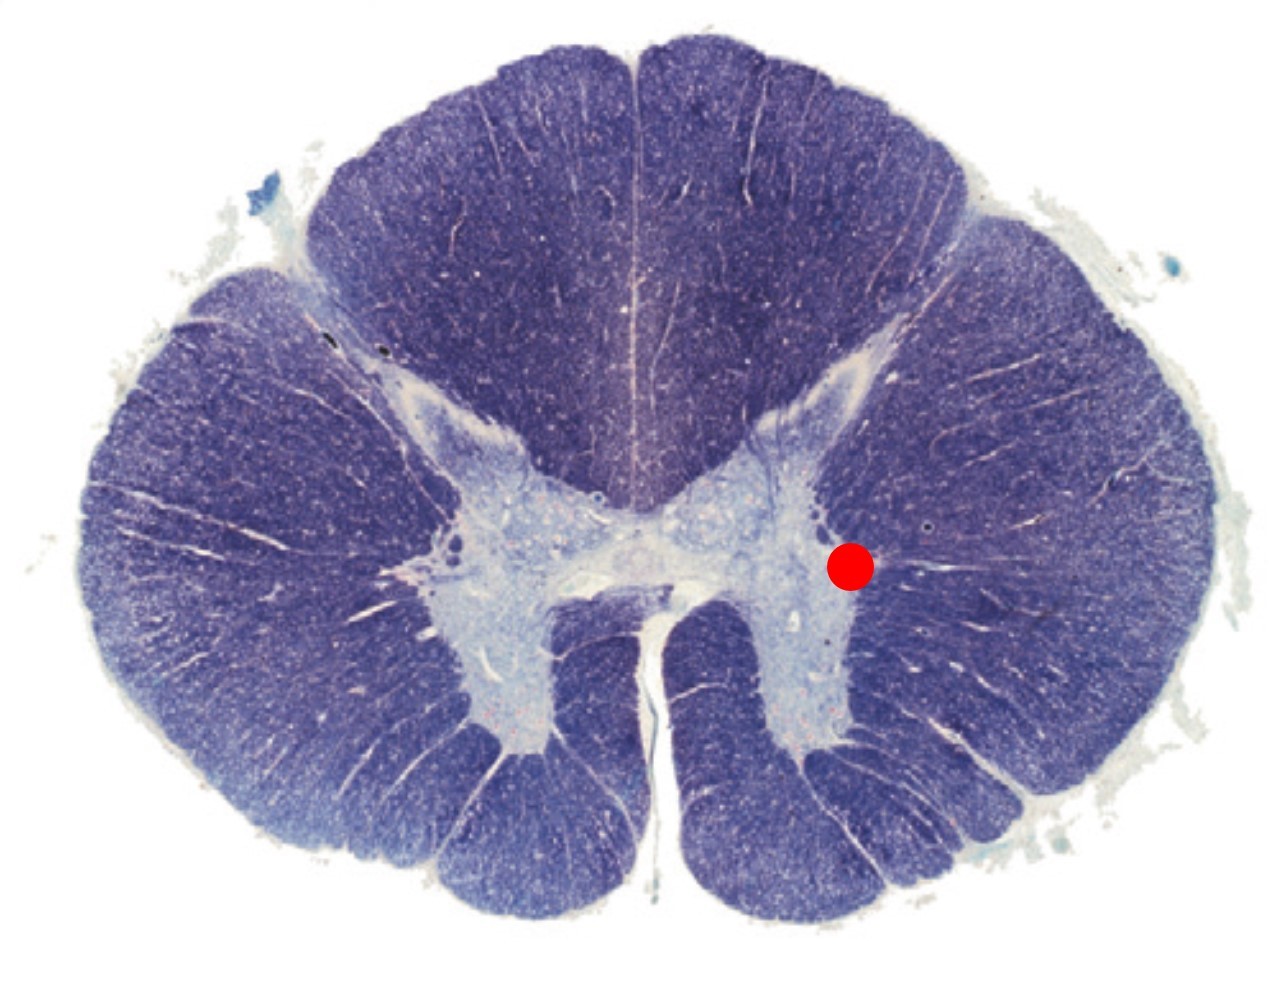

The region of the spinal cord indicated by the red spot:

Contains autonomic neurons

Contains somatic motor neurons

Is present at all levels of the spinal cord

Is the substantia gelatinosa

The substantia gelatinosa is located in which Rexed lamiae of the spinal cord grey mater?

II